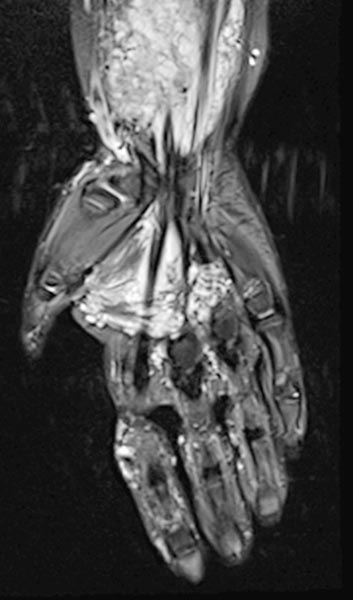

Die venöse Malformation zeigt in der T2-gewichteten, fettunterdrückten MRT eine tiefe Ausdehnung im Bereich der tiefen Flexorensehnen der Hand und des Unterarmes.

Am distalen Unterarm rechts im Bereich der hauptsächlichen Ausdehnung der Schwellung zeigt sich das Ausmaß der venösen Malformation vorwiegend im Bereich der Flexoren. Stark hyperintenses MRT-Signal in der T2w-Fettsättigung. Die gesamte beugeseitige Muskulatur ist durchsetzt.